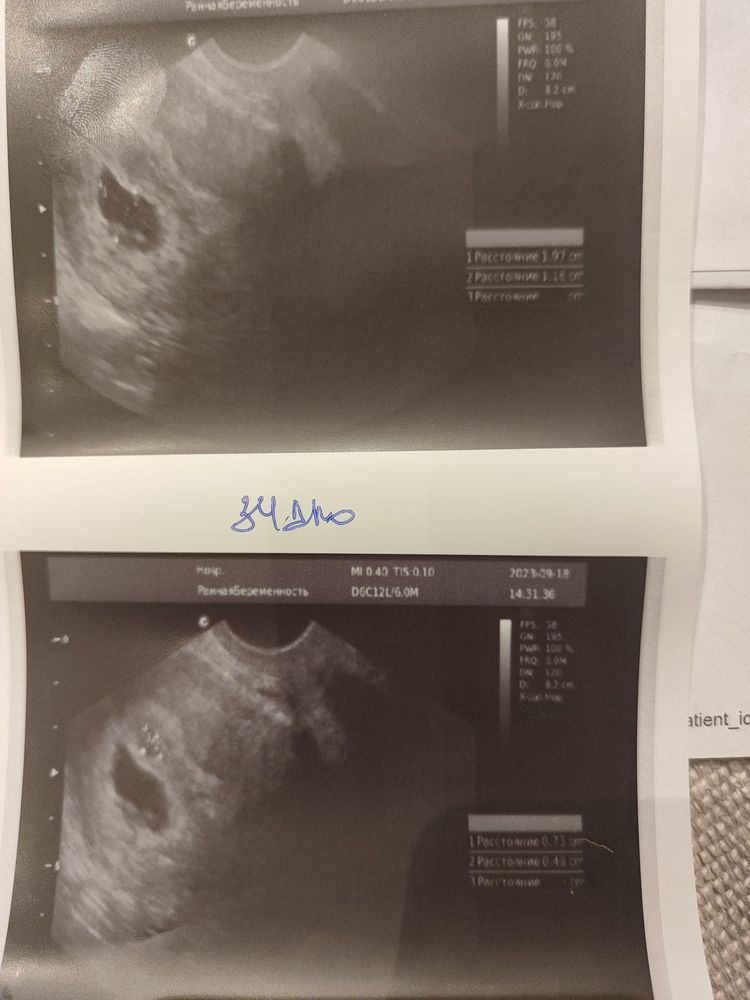

Была на УЗИ:

34 дпо- (6.4 нед) эмбриона нет, жм+(сомневается врач) ПЯ 20.0 по фото видно что округляется (ХГЧ 60тыс).

Прикрепляю УЗИ 32 дпо и 34 дпо-... Может кто-то что-то поймет.

УЗИ где виден желт.мошок и какой-то бугорок который растет